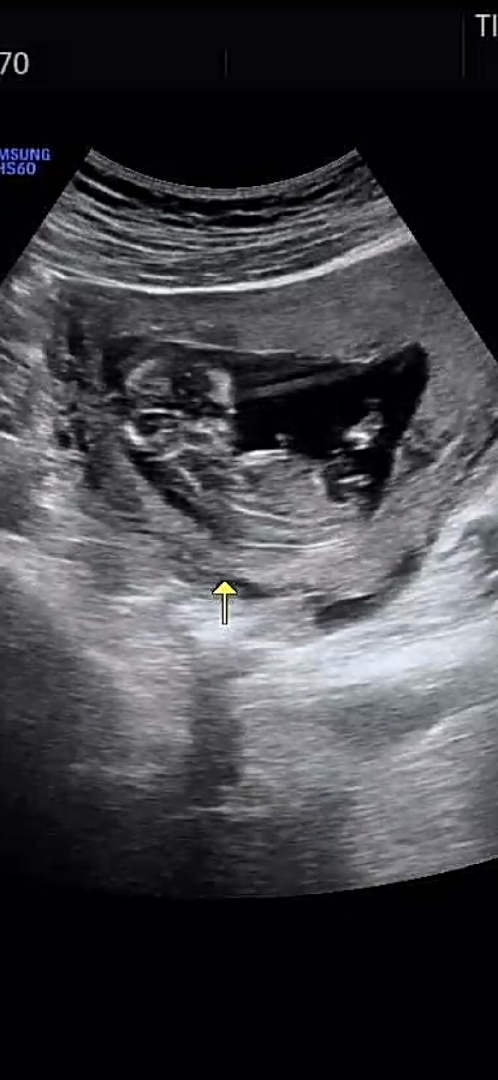

딸인거같죠???

원래.. 각도법 고순데 막상 제아이 보려니 잘모르겠네영 ㅠ 딸인거같기도..하구 어때보이세요??